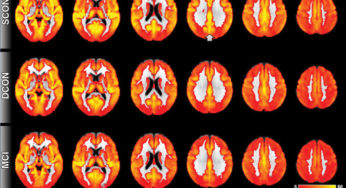

En los ratones con Alzheimer, memoria restaurada con medicamento contra el cáncer

La memoria así como las conexiones entre las células cerebrales se restauraron en ratones con un modelo de un determinado… Read More